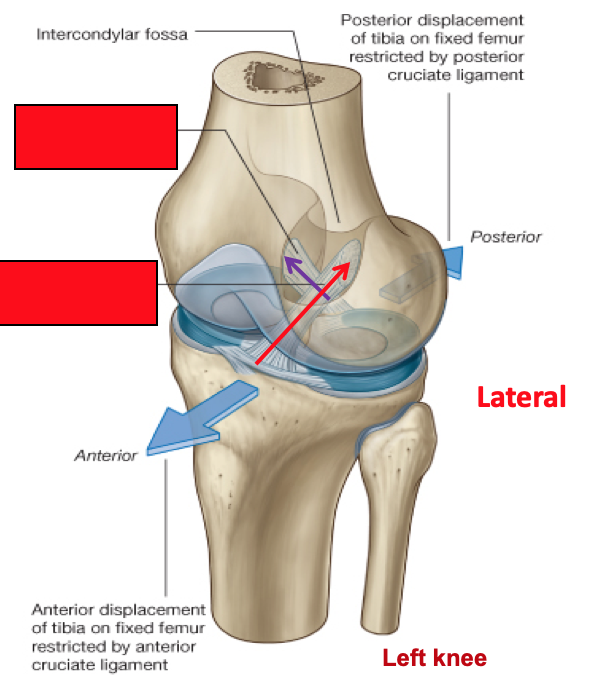

Label the diagram as if you were looking down onto the inside of a left knee

Where do the menisci attach to?

Where are they thicker?

The external edges attach to the fibrous capsule of the joint

They are crescent shaped discs of fibrocartilage that are ticker at the external margins